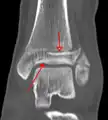

Fracture of both sides of the ankle with dislocation as seen on anteroposterior X-ray. (1) fibula, (2) tibia, (arrow) medial malleolus, (arrowhead) lateral malleolus

On X-rays, there can be a fracture of the medial malleolus, the lateral malleolus, and/or of the anterior/posterior margin of the distal tibia. The posterior margin (known as the posterior malleolus) is much more frequently injured than the anterior aspect of the distal tibia. If both the lateral and medial malleoli are broken, this is called a bimalleolar fracture (some of them are called Pott's fractures). If the posterior malleolus is also fractured, this is called a trimalleolar fracture.